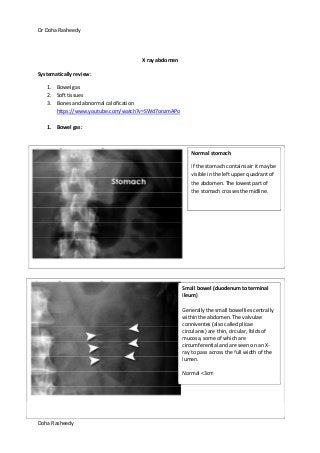

Normal stomach

If the stomach contains air it may be

visible in the left upper quadrant of

the abdomen. The lowest part of

the stomach crosses the midline.

Small bowel (duodenum to terminal

ileum)

Generally the small bowel lies centrally

within the abdomen. The valvulae

conniventes (also called plicae

circulares) are thin, circular, folds of

mucosa, some of which are

circumferential and are seen on an X-

ray to pass across the full width of the

lumen.

Normal <3cm